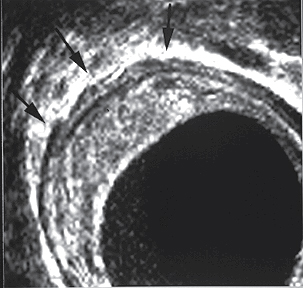

• Endoscopic ultrasonography showing a rectal carcinoma. The normal hypoechoic boundary of the muscularis propria is expanded and irregular (arrow), indicative of tumor infiltration into the perirectal tissue. here Ultrasonographic staging as a T3 cancer was confirmed by surgical pathology. here

• Transrectal ultrasound image demonstrates a mass arising in the anterior wall of the rectum and extending into the muscularis propria layer (arrows). This finding is consistent with a stage T2 tumor here